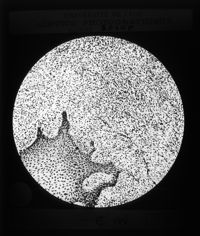

Image[Plaque diapositive. Tissus bucco-dentaires.]